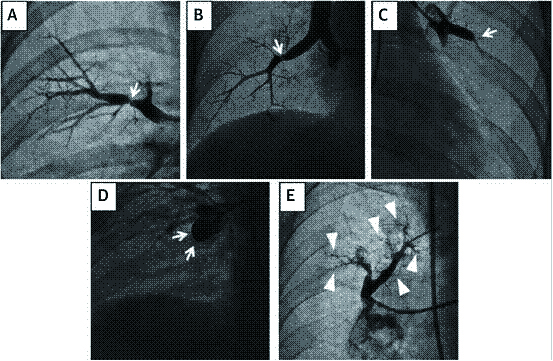

CTEPH肺动脉造影的特征性表现包括:带状或网状,内膜不规则,囊袋状缺损,血管突然狭窄,肺动脉完全阻塞等[39](图 3)。

根肺动脉造影的影像学变现的患者病变部位的受损程度及远端血流情况,以新的形态学标准分为以下五类:A型,环状狭窄;B型,网状病变;C型,次全病变;D型,完全闭塞;E型,弯曲病变[40] (图 4)。

根据血栓的位置,UCSD建议将CTEPH中的肺血栓栓塞分为各级:Ⅰ级:累及肺动脉主干;Ⅱ级:始于肺动脉段;Ⅲ级:始于肺动脉亚段;Ⅳ级:仅限于肺动脉亚段。此外,IC级为单只肺动脉完全闭塞,右肺动脉或左肺动脉完全闭塞,0级则未见相应肺内CTEPH(图 5)。值得注意的是,这种分类是在PEA术中进行的分类。随着成像方式的改进,术前预测疾病水平的能力有所提高,尽管不是所有情况都能进行预测。对于Ⅲ至Ⅳ级病变即使专业性更强的术者进行手术,并发症的发生率也更高,但手术成功后血流动力学仍有望得到改善。